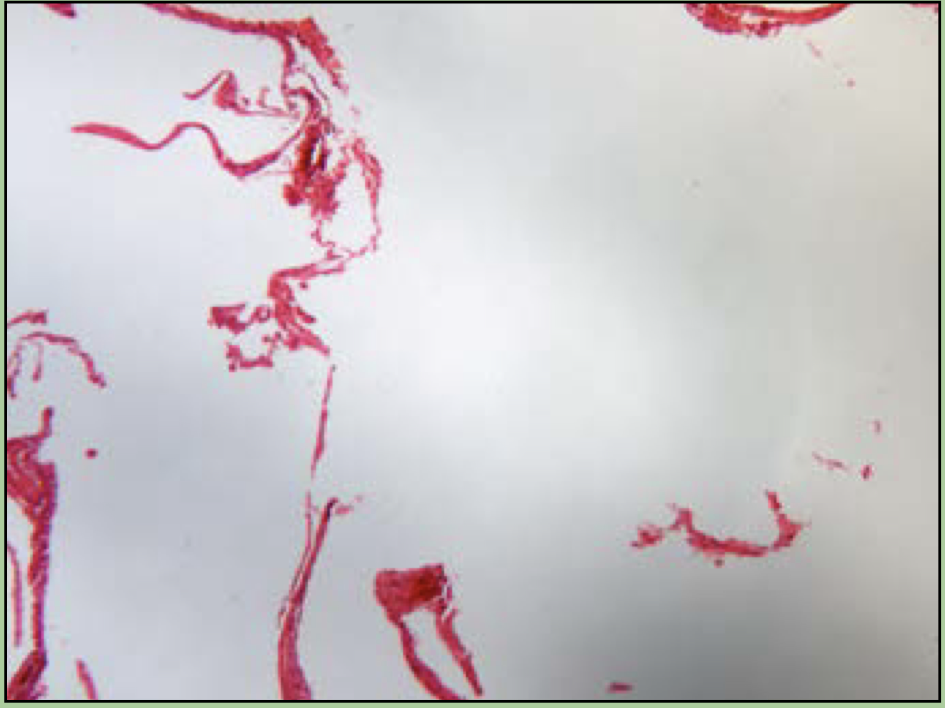

What disorder is this?

Cirrhosis

fibrous fatty deposits in liver

87

New cards

Hepatitis

viral infection of the liver